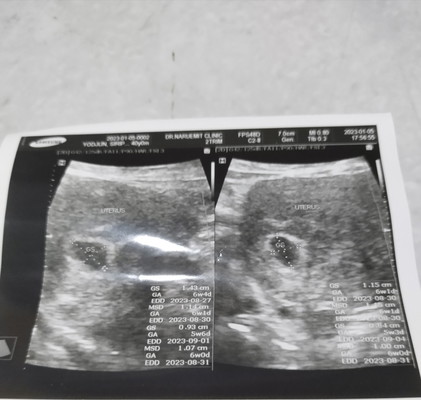

ยังไม่ได้ฝากครรภ์ ด้วยความกังวลเลยไปหาหมอก่อนคะ พอดีฉี่เสร็จแล้วมีเลือดสีน้ำตาลติดทิชชู่ แล้วก็ปวดท้องเหมือนเป็นประจำเดือน โล่งอกคะที่ไม่ได้ท้องนอกมดลูก แต่นับจากปจด.ล่าสุด12/11/65ก็7สัปดาห์กว่า แต่พอซาวด์อายุครรภ์แค่6สัปดาห์คะ หมอเลยบอกว่ายังไม่เห็นเด็กและหัวใจนะต้องรออีก2สัปดาห์ค่อยซาวด์ใหม่ เลยถามว่าเลือดที่ออกภาวะแท้งไหม หมอบอกไม่น่าใช่น่าจะเป็นเพราะตัวอ่อนกำลังฝังตัว และถุงตั้งครรภ์ยังสวยอยู่ คลายกังวลได้เปราะนึงเลยคะ